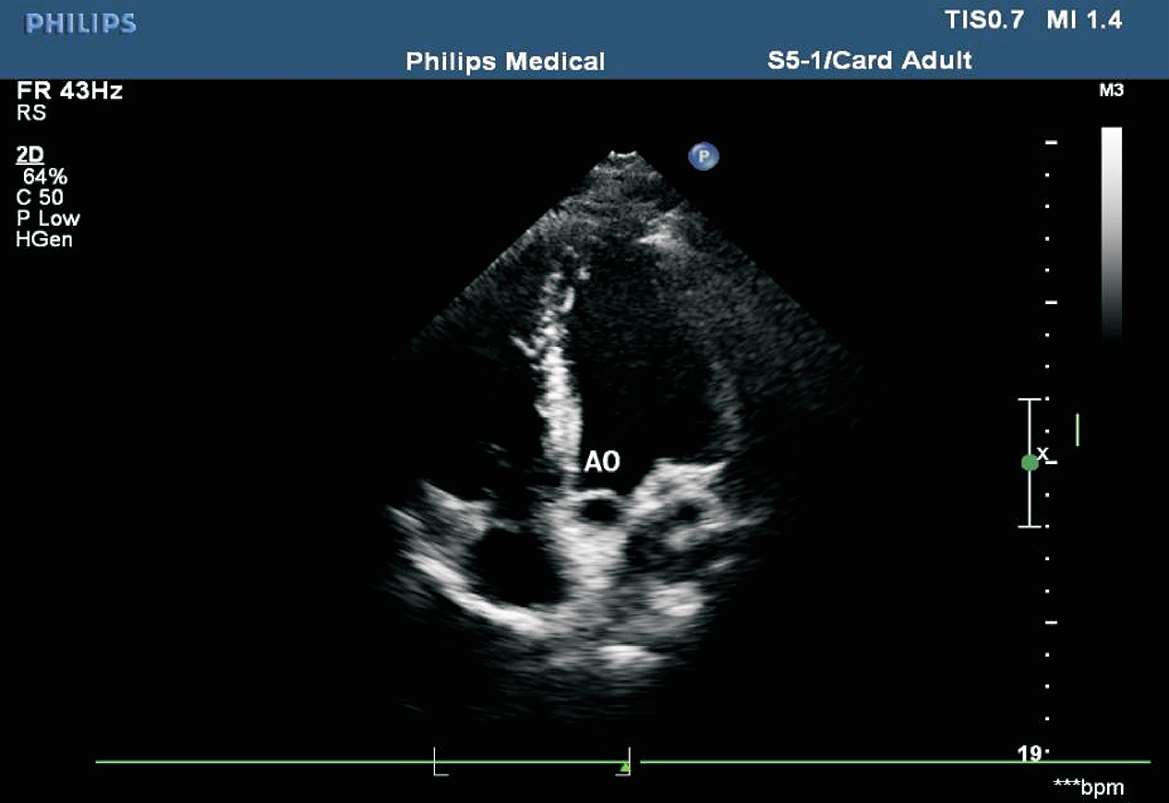

患者取左侧卧位或平卧位,探头置于胸骨左缘第2~3 肋间,声束垂直于胸骨旁左心室长轴切面。在此切面可观察主动脉瓣的形态、厚度、回声强度及开闭状态,右心室流出道与肺动脉干有无增宽、狭窄,降主动脉与肺动脉之间有无异常通道,肺动脉瓣的形态及活动(见图1-27)。正常主动脉瓣呈三瓣叶,收缩期开放为“▽”形,舒张期关闭为“Y”形(见图1-28)。

图1-27 心底大动脉短轴切面(RA:右心房;RV:右心室;PA:肺动脉;AO:主动脉;LA:左心房)

图1-28 心底大动脉短轴切面主动脉瓣呈三瓣叶,舒张期关闭为“Y”形